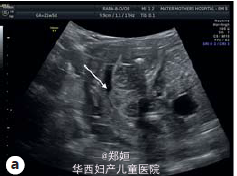

22岁初产妇,孕21周,因胎儿膀胱未见、羊水过少、胎儿腹部囊性结构就诊

B超提示羊水过少和未见胎儿膀胱,肾窝内未见肾脏,但是在腹腔和盆腔可见三个囊性结构,外生殖器性别不明 胎儿MRI提示有泌尿生殖器畸形

临床诊断为胎儿泌尿生殖器畸形 患者要求生产,在孕35周,顺产生下一3140g男婴